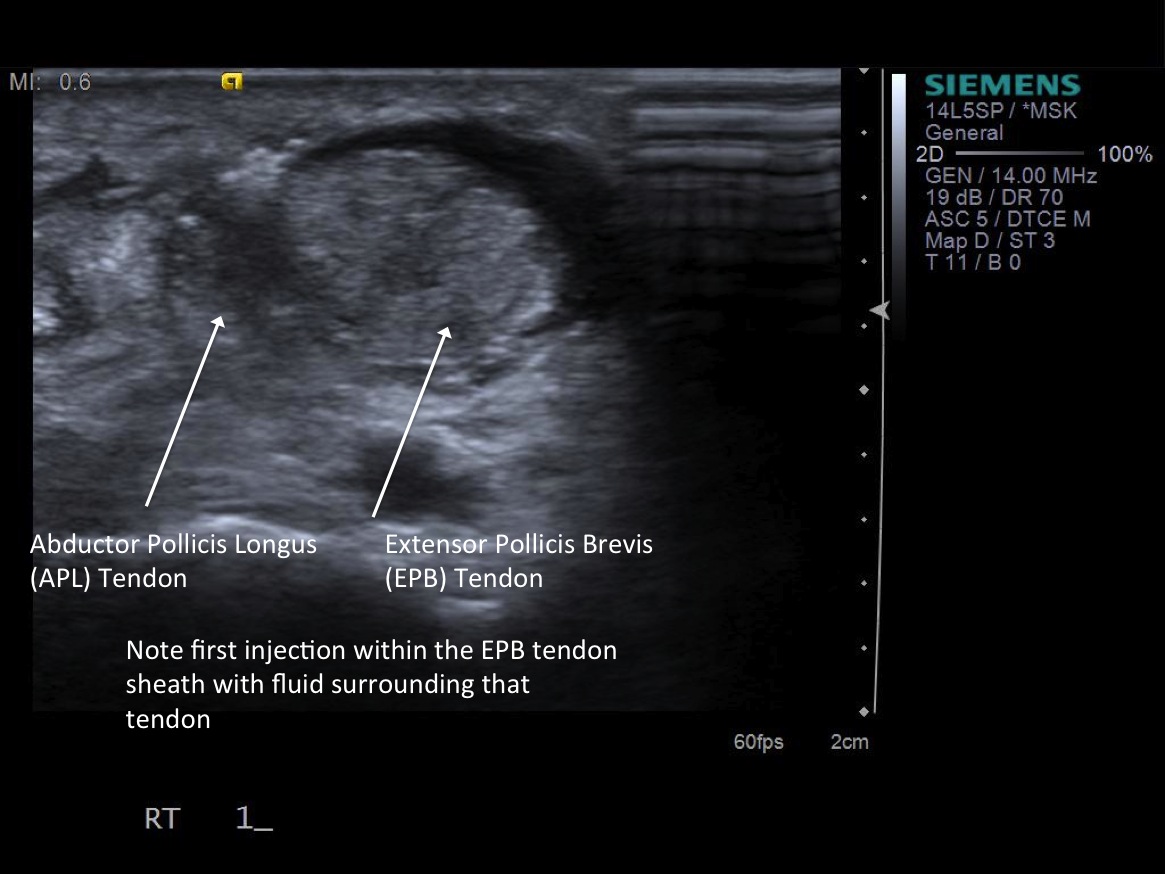

6. Inject 1% lidocaine superficially with 25g 1.5” needle. Advance needle deeper surface of the 1st extensor tendon sheath. Oftentimes, the APL and EPB tendons are in separate sheaths and may require separate injections. Then, unscrew syringe from needle for greater needle control.

7. Under ultrasound guidance,advance needle into the 1st extensor tendon sheath. In this case the APL and EPB have separate sheaths and require their own injections. Test inject with 1% lidocaine. If no resistance, switch 1% lidocaine for injectable steroid mixture. If there is resistance, reposition needle and test inject again. Inject 1 cc of injectable steroid/anesthetic mixture.